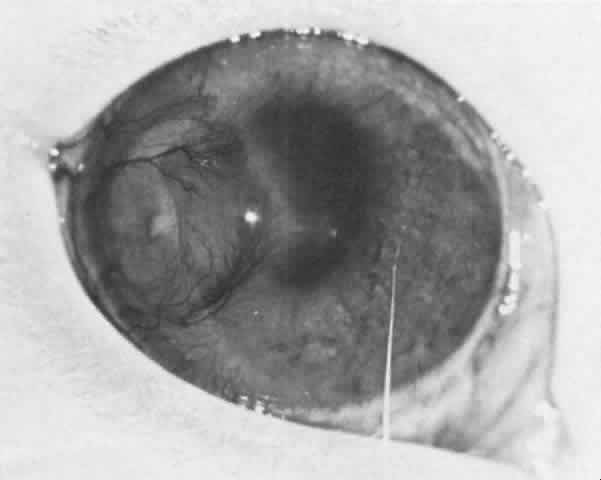

The behavior of corneal allografts is illustrative. When the results of one series were averaged, hosts with avascular corneal beds had rejected 3.5% of the grafts in 10 months, hosts with mildly vascularized corneal beds had rejected 13.3% in 4 months, and hosts with moderately vascularized corneal beds had rejected 65% in 2 months.4 It has also been shown that in experimental animals, 95% of lamellar corneal grafts and 75% of penetrating grafts placed in avascular beds survived for long periods of time. This was true even in animals sensitized by permitting them to reject large skin grafts from the same donors that provided the corneal buttons. These amply sensitized animals could not convey the sensitized lymphocytes to their avascular corneas.5 It is also significant that the graft rejection line usually starts at the site of maximum vascularization (Fig. 2).

Fig. 2. A rabbit eye with a mild corneal graft reaction characterized by neovascularization and opacification of the donor tissue. A significant part of the recipient cornea remains uninvolved in this reaction.